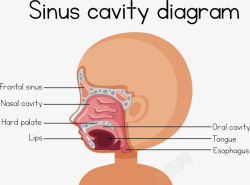

人体鼻咽喉结构矢量图